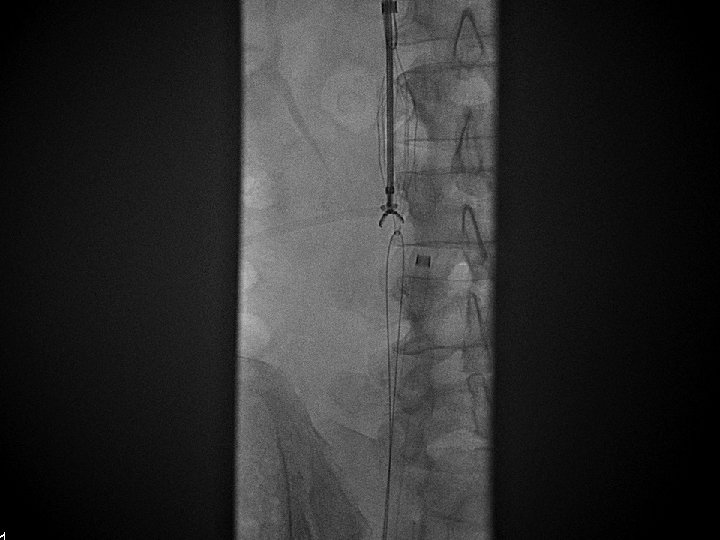

IVC Filter Removal Straight forward and Complex

Equipment Sheaths Directional catheters Directional guidewires Loop snares Grasping devices Baskets

Removal of an “Intravascular Foreign Body” Straight forward Loop snare Grasping device Complex Multiple devices used including angioplasty balloons, bronchoscopy forceps, and the“in situ” snare technique.

Retrieval with a snare and a long sheath or guiding catheter Günther Tulip (Cook) Celect (Cook) Opt Ease (Cordis Endovascular) Option (Angiotech) G 2 X, Eclipse, Meridian (Bard)

Snare Retrieval En. Snare